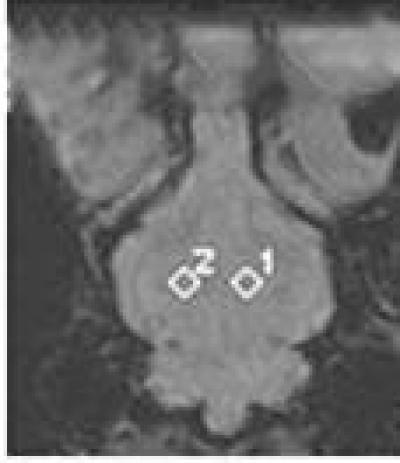

Acute hemorrhagic anemia can decrease blood flow and oxygen supply to brain, and affect its physiological function. Detecting changes in brain function in patients with acute hemorrhagic anemia is helpful for preventing neurological complications and evaluating therapeutic effects. Susceptibility-weighted imaging (SWI) imaging is a novel, non-invasive method for detecting changes in cerebral oxygen levels that may provide more detailed information regarding cerebral blood flow in patients with hemorrhage. Dr. Jun Xia, Second People's Hospital of Shenzhen City, First Affiliated Hospital of Shenzhen University, China and his team found that the SWI signals from the frontal cortex, temporal lobe, and thalamus after the second, third, fourth and fifth bloodletting procedures were significantly lower compared with the corresponding control (pre-bleed) values and that the contrast between cerebral gray and white matter was higher after bloodletting (particularly after the fourth and fifth procedures) than beforehand. These results provide the information regarding pathophysiological changes of the brain after acute hemorrphagic anemia. These findings were published in Neural Regeneration Research (Vol. 9, No. 9, 2014).

Article: " Susceptibility-weighted imaging is suitable for evaluating signal strength in different brain regions of a rabbit model of acute hemorrhagic anemia," by Jun Xia1, Ni Xie2, Anyu Yin1, Guozhao Teng3, Fan Lin1, Yi Lei1 (1 Department of Radiology, Second People's Hospital of Shenzhen City, First Affiliated Hospital of Shenzhen University, Shenzhen, Guangdong Province, China; 2 Biobank, Second People's Hospital of Shenzhen City, First Affiliated Hospital of Shenzhen University, Shenzhen, Guangdong Province, China; 3 Medical Record and Statistics Room, Second People's Hospital of Shenzhen City, First Affiliated Hospital of Shenzhen University, Shenzhen, Guangdong Province, China)